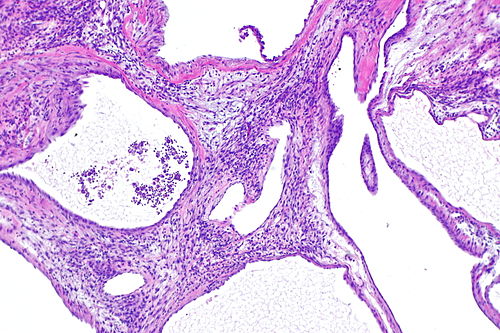

Cystic nephroma -- low mag.jpg

Low magnification. H&E stain.

CYSTIC NEPHROMA / MIXED EPITHELIAL STROMAL TUMOUR

Cystic nephroma and mixed epithelial stromal tumour were described as separate entities. The WHO classification of renal neoplasia (known as the Vancouver classification) lumps them together.[1]

Cystic nephroma/mixed epithelial stromal tumour is a rather awkward name. One cheeky article suggests the term renal epithelial and stromal tumour (abbreviated REST) to put the issue to rest.[2]